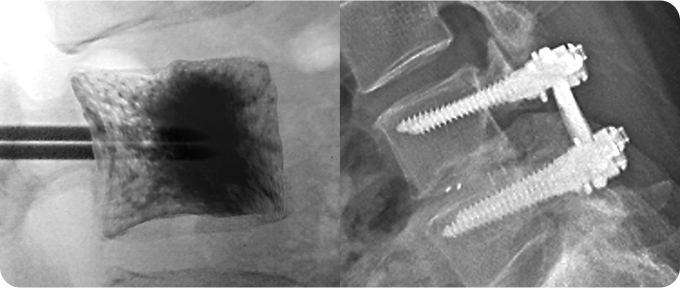

척추 성형술&고정술 사진

3

척추 성형술&고정술

척추 성형술은 의료용 시멘트를 골절 부위에 주입해 통증을 완화하고 척추를 안정화하는 방법입니다. 풍선 척추 성형술은 척추 높이를 복원한 뒤 시멘트를 채워 안정성을 높입니다. 척추 고정술은 금속 기구를 사용해 척추뼈를 고정하며 불안정을 해소합니다. 두 방법 모두 환자의 상태와 골절 정도에 따라 선택됩니다.